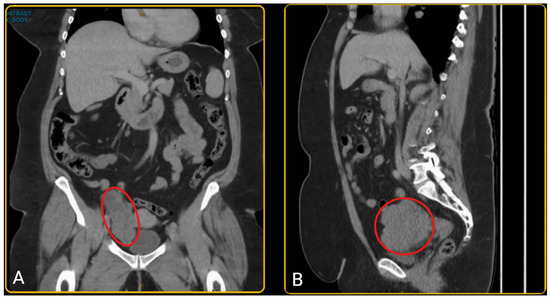

A woman in her late 50s presented with a history of post-menopausal bleeding and pelvic pressure. A pelvic ultrasound and CT scan showed a right adnexal mass measuring 103 × 98 × 50 mm (Figure 1). The mass had an irregular wall and a solid component. However, her tumour markers were normal (CA 125 = 13; Ca 19-9 = 22; CEA = 2.5; AFP = 7; RMI = 111). She was pre-emptively diagnosed with an ovarian tumour; however, since the diagnosis was not established, pre-operative biopsy was not performed due to the risk of tumour seeding and technical challenges. The patient was planned for hysteroscopy, endometrial sampling, laparoscopy +/− bilateral salpingo-oophorectomy after a detailed discussion of the diagnostic uncertainty and potential histopathological findings. Given her age, post-menopausal status, and clinical presentation, she understood the rationale for surgical intervention and provided informed consent for the proposed plan.

Figure 1.

(A) The coronal view of the pelvic CT scan; (B) the sagittal view of the pelvic CT scan showing a mass in the right lower quadrant of the abdomen, anteromedial to the iliac vessels and posterior to the bladder, consistent with a right adnexal mass (outlined in red). The mass measures 103 × 98 × 50 mm, with a well-demarcated, irregular border and has a heterogenous composition with varying internal density.